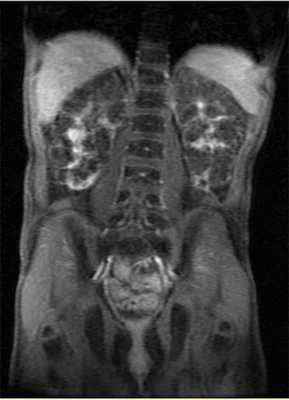

Рисунок 7 | МРТ, корональная Т2-проекция, пациент с ПБП-АР.

b) Корональное Т2-взвешенное изображение брюшной полости:

— стрелкой показано кистозное веретенообразное расширение желчных протоков;

— стрелкой по типу наконечника стрелы — нефромегалия с маленькими цистами;

✱ — спленомегалия.